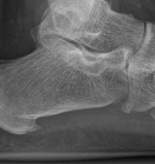

Routine removal of implants is not performed unless they are prominent and symptomatic but only after healing is complete, so at 12–18 months at the earliest. This patient showed good radiographic healing at the 6-month postoperative review (Fig 2.3-4). He regained full range-of-ankle motion at 6 months postoperative (Fig 2.3-5).

Fig 2.3-4a–b Postoperative x-rays at 6 months show fracture healing without loss of fixation.